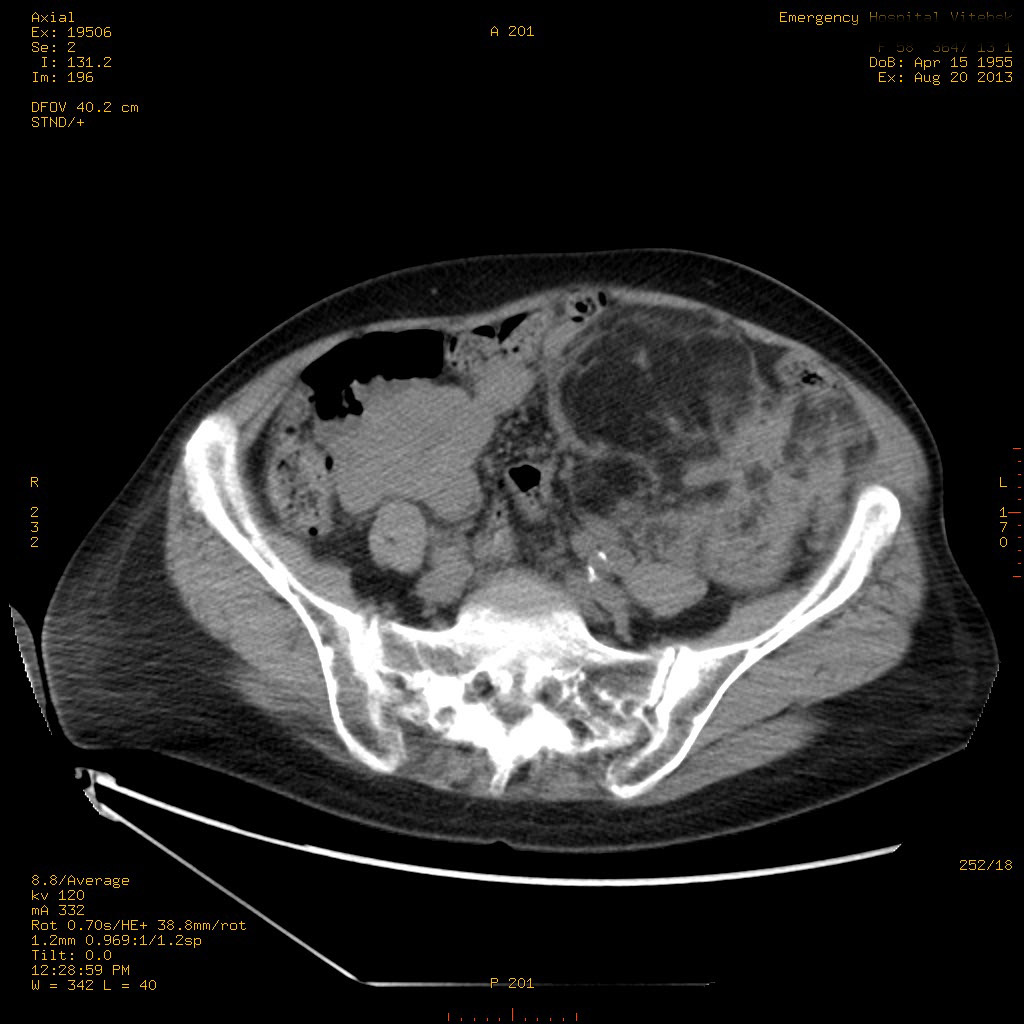

УЗИ почек - туберозный склероз

Пожилая женщина с нормальными мочевиной и креатинином.

Ангиомиолипоматоз почек , думаю компонент туберозного склероза.

Да, туберозный склероз.

Случай консультирован на кафедре радиологии Католического университета г.Лёвен (Бельгия) - зав каф. профессор Р.Оуен.